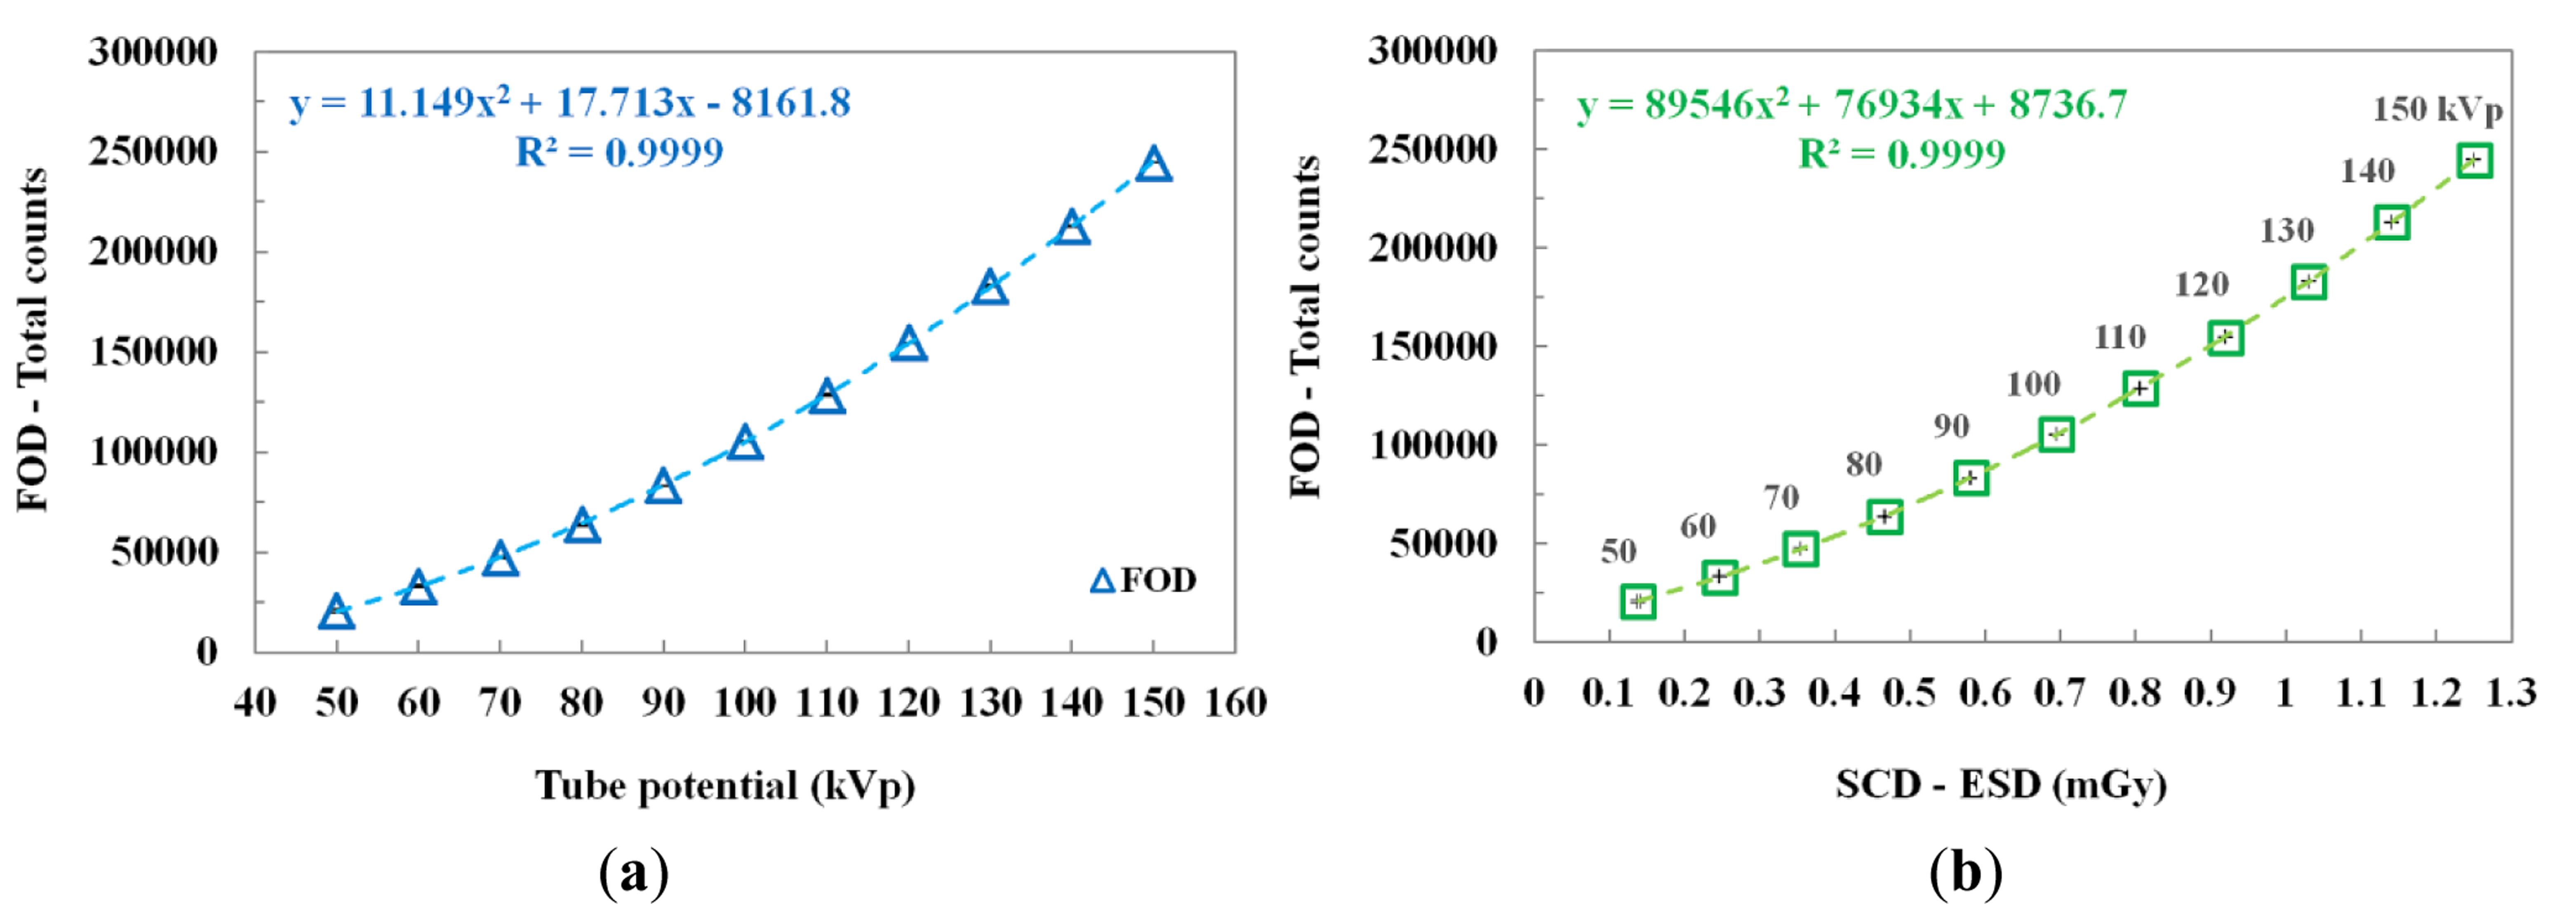

The scintillating light and the ESD were measured simultaneously by increasing the tube potential from 50 to 150 kVp in increments of 10 kVp while keeping other exposure parameters constant. As can be seen in Figure 4a, according to the increase of the tube potential, the total counts of the FOD increase according to a quadratic equation because the plastic scintillator has a nonlinear scintillation response to low-energy levels of diagnostic radiation [16,20,21]. Figure 4b plots the relationship between the total counts of the FOD and the ESDs measured using an SCD as a function of the tube potential. The total counts and ESDs increased over the tube potential range as the tube potential increased. The best fit line and the square of the correlation coefficient (R2), which refers to the accuracy of matching between the measured datum and the fitting line, are presented in Figure 4.

In this study, we fabricated a miniature FOD system using a PSF, a POF, and an MPPC module for measuring real-time ESD with minimization of artifacts in the DR image during medical imaging tasks. While varying the exposure parameters of a DR system, we measured the scintillating light related to the ESD using the sensing probe of the FOD, which was placed at the center of the beam field on the anthropomorphic thorax phantom. From the experimental results, the total counts of the proposed FOD system were changed in a manner similar to the ESDs including backscatter simultaneously obtained using a conventional SCD. In particular, we demonstrated that the total counts of the FOD are only affected by the ESD values even though each exposure parameter is changed independently. As functions of each exposure parameter, such as tube potential, tube current, irradiation time, and FSD, the relationships between the total counts of FOD and the ESDs and the best fit lines are presented in Figures 4, 5, 6, and 8 and their R2 values are very close to 1. In the range of ESD values less than 1 mGy, the mathematical relation between the total counts of FOD (x) and the ESDs (y) is y = 68939x2 + 84559x + 16099, regardless of the exposure parameters. However, this relation has a low accuracy because R2 is found to be 0.9794. Therefore, it is necessary to optimize hardware and software of the FOD system for measuring ESD with a high accuracy. Next, DR images were also obtained using a flat panel detector of the DR system to evaluate the effects of the dosimeter on image artifacts during PA chest radiography. The proposed FOD minimally affected the diagnostic information of radiation images while the SCD caused serious image artifacts due to its large size and high-atomic-number materials.